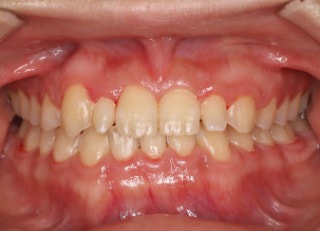

上顎2番矮小歯右下2番先天欠如

解説:下顎前突上顎劣勢長傾向で、上顎両側2番が矮小歯、右下2番先天欠如症例なので、上下前歯の幅径の比率を調節する必要があるケースです。(ご本人のご都合で治療中に来院できない期間がありました)

治療前